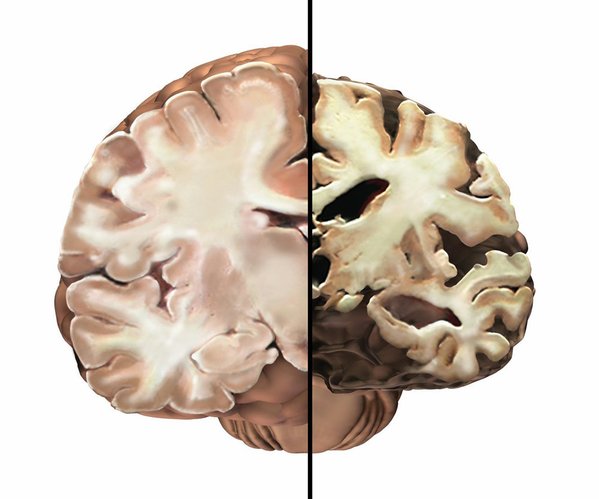

وقال الخبراء إن الشيء الوحيد المشترك بين جميع الأفراد المصابين بألزهايمر، هو فقدان ثابت للخلايا العصبية الرئيسية المرتبطة بارتفاع ملحوظ في البروتينات غير الطبيعية، خاصة بيتا أميلويد وتاو، حيث يتكتلان ويتشابكان بطرق تؤدي إلى إتلاف الخلايا بشكل مباشر.